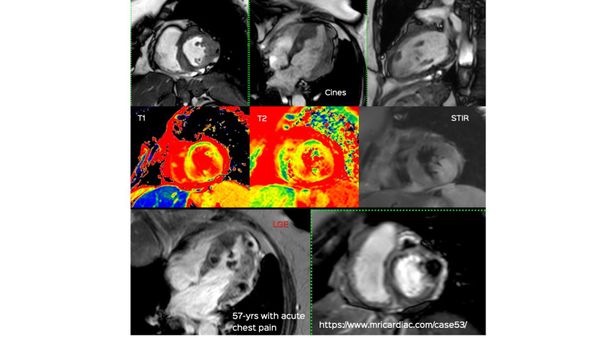

This 57-years old presented with acute chest pain. She was diagnosed to have a non-STEMI infarct. Coronary angiography and echo were done. Based on the echo findings, an MRI was done, which uncovered a myriad of findings. The video explains the rest. Do Subscribe to View - It's